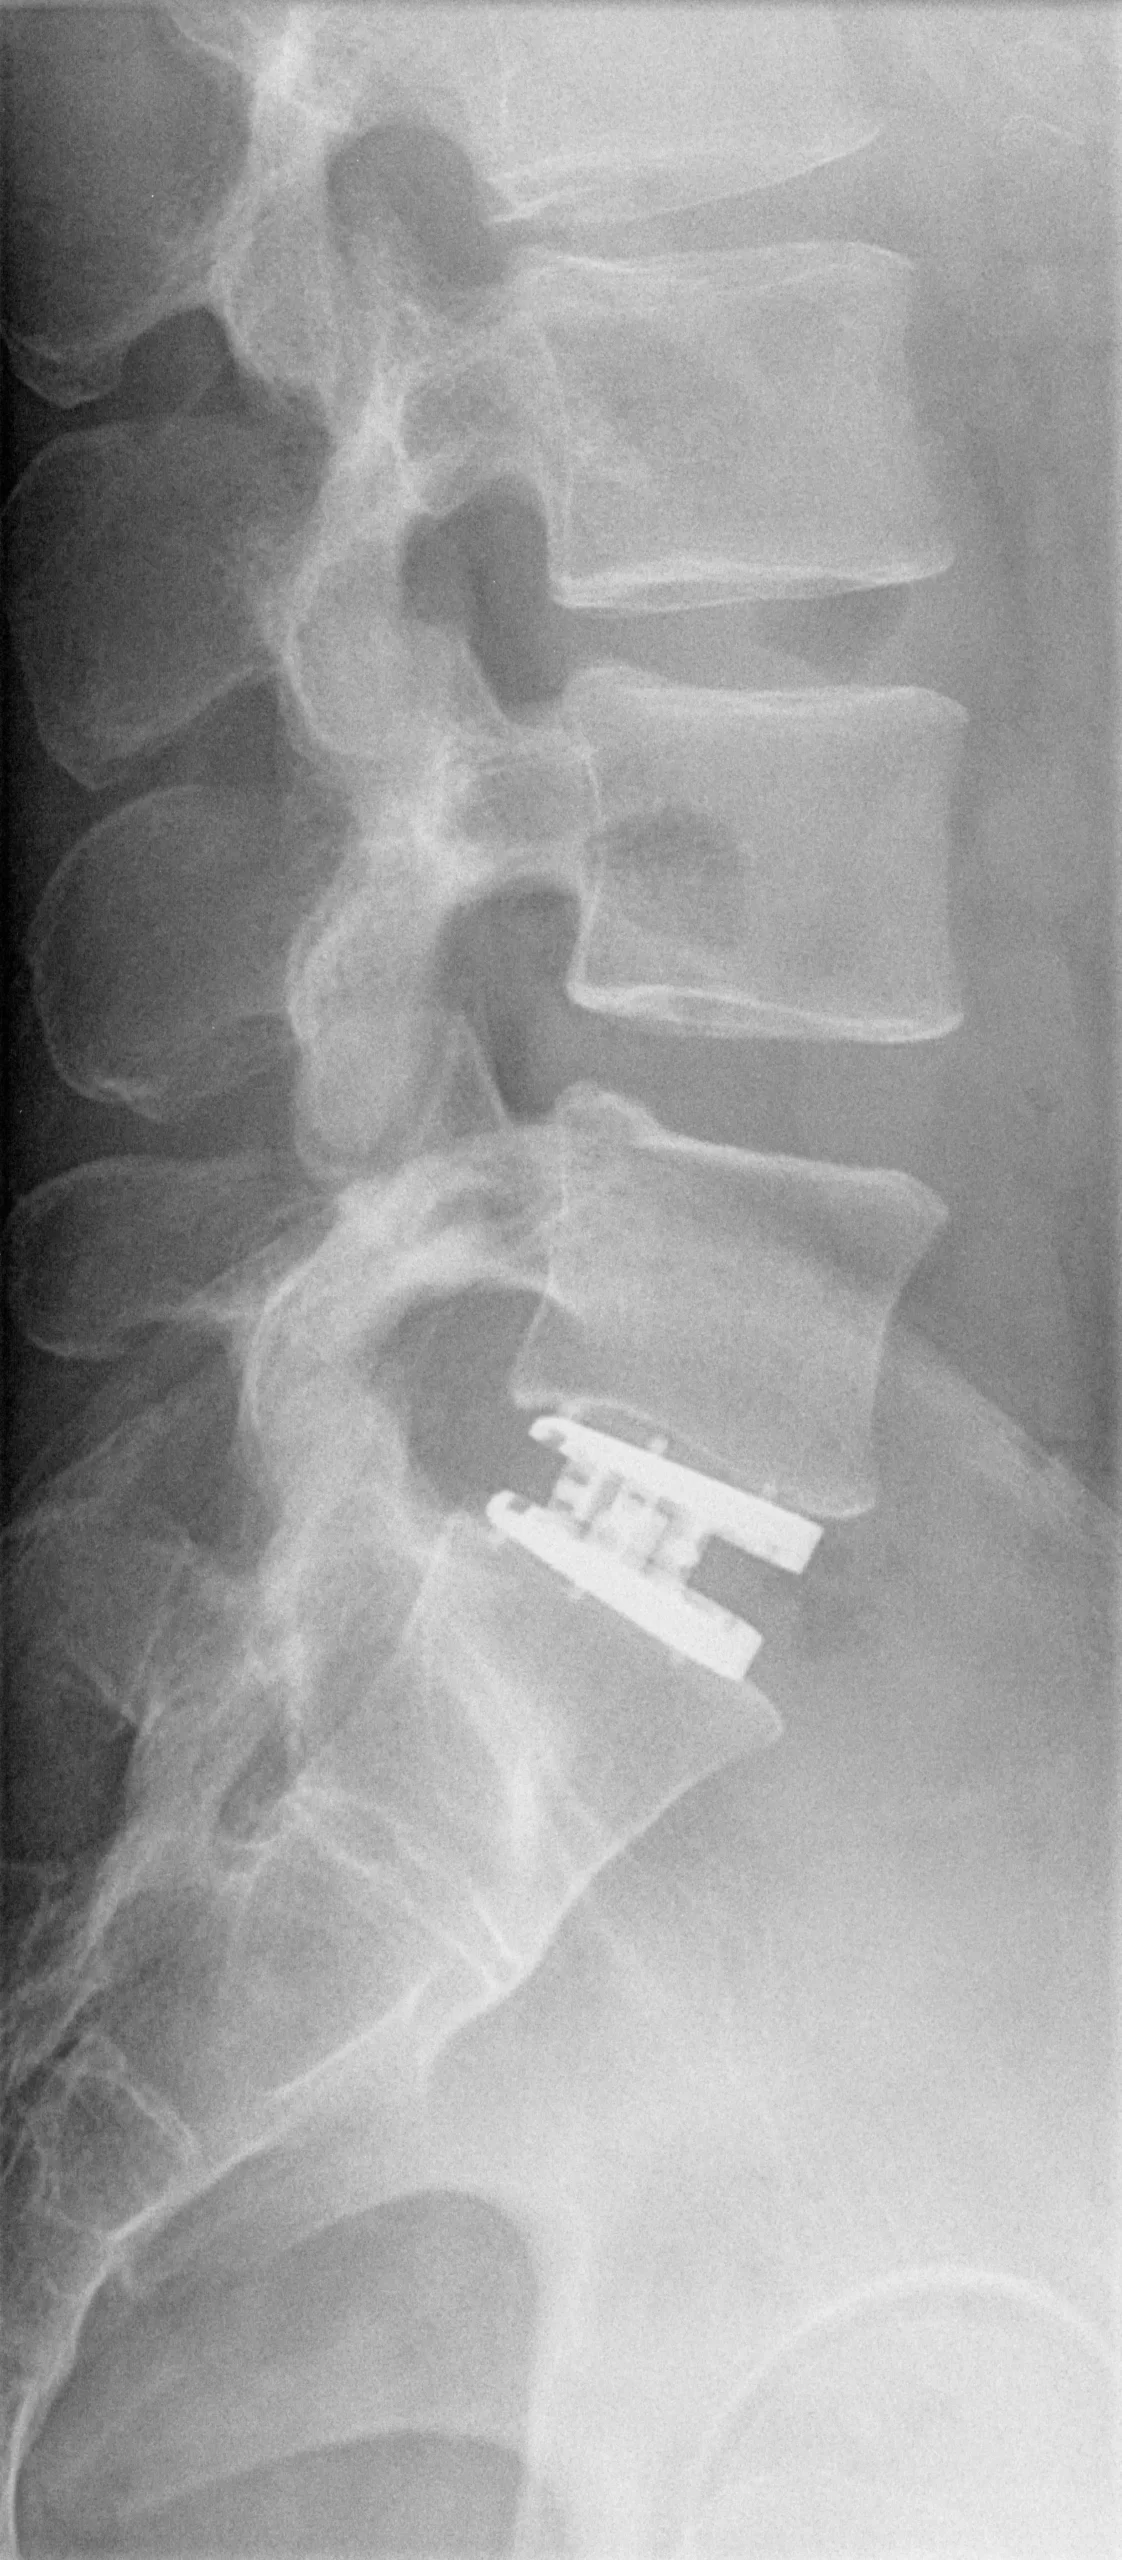

Pic #1 Post OP lat.

My artificial disc replacement was for my L5/S1

My artificial disc replacement was for my L5/S1. My back and disk pain was terrible. Doctors only gave me pain medication that did not fix the underlying problem. The pain and immobility got so bad that I could barely pass my physical fitness tests for work and it was difficult to travel due to having to carry large amounts of baggage.